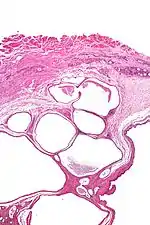

| Micrograph of a cystic tumour of the atrioventricular nodal region. H&E stain. | |

Cystic tumours of the atrioventricular nodal region, true to their name, have cystic spaces, which are lined by a single layer of histomorphologically benign epithelial cells. The appearance is similar to that of lymphangioma and this is a name that has been used for this tumour.[1]